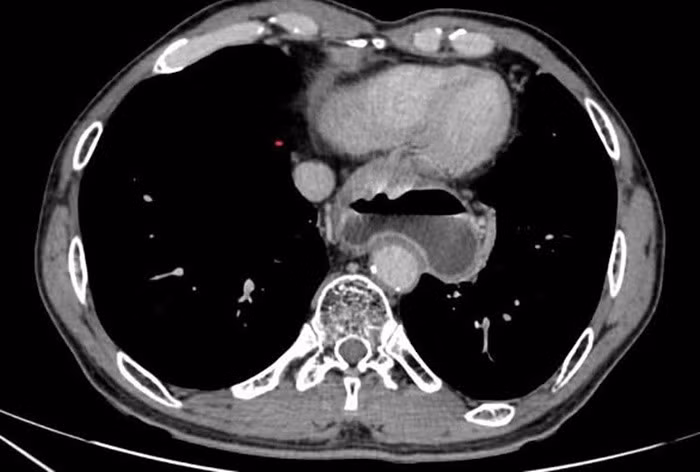

2.jpg

Bệnh nhân được chẩn đoán ung thư ống dạ dày cT3N0M0 trên nền bệnh nhân từng điều trị ung thư thực quản./Ảnh Bệnh viện Ung bướu Hà Nội

Kết quả giải phẫu bệnh xác định, ung thư tế bào nhẫn ống dạ dày, một thể ung thư tiến triển nhanh, khó điều trị. Sau khi chuyển đến Bệnh viện Ung bướu Hà Nội, các bác sĩ chẩn đoán: Ung thư ống dạ dày cT3N0M0 trên nền bệnh nhân từng điều trị ung thư thực quản. Để đảm bảo điều trị triệt để, phương án được đưa ra là cắt bỏ toàn bộ ống dạ dày, vét hạch triệt căn và tạo hình lại thực quản bằng đoạn đại tràng trái.

Trong quá trình phẫu thuật, các bác sĩ đã đưa đoạn đại tràng lên ngực và cổ để nối với phần còn lại của thực quản, thay thế hoàn toàn chức năng tiêu hóa của đoạn dạ dày bị cắt bỏ. Sau mổ, bệnh nhân phục hồi tốt, ăn uống trở lại sớm, ổn định toàn trạng và được xuất viện sau 8 ngày điều trị nội trú.